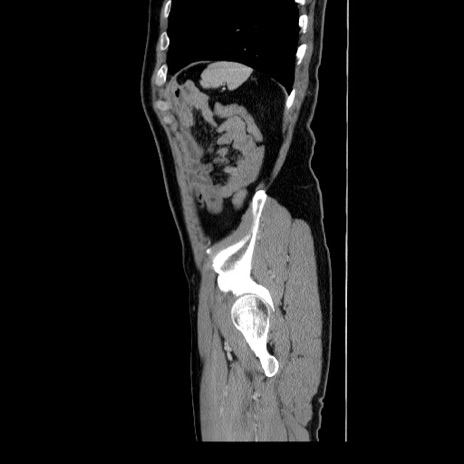

症例34(矢状断像)

【症例】60歳代 男性

【主訴】右鼠径部膨隆

【現病歴】1年程前より右鼠径部膨隆あり。自己にて還納可能だったため放置していた。3時間前より右鼠径部の脱出を認め、還納困難となり受診。

【身体所見】右鼠径部に小児頭大の膨隆あり。弾性硬であり、用手還納は困難。左鼠径部にも膨隆を認める。脱出はなし。